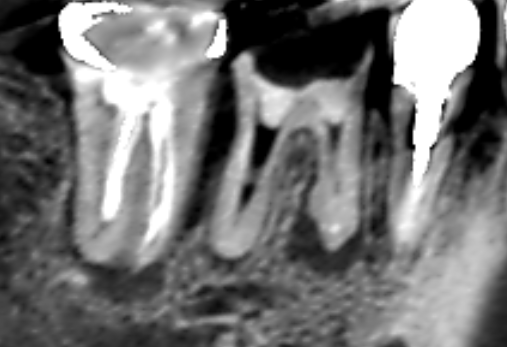

実際に「根管」の画像をご覧頂きましょう。歯の中にある黒い筋が根管です。